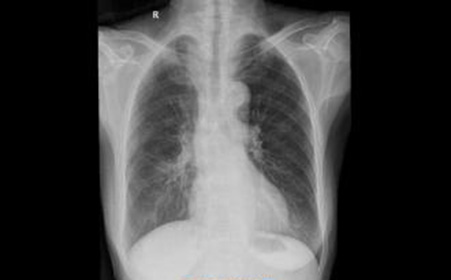

肺气肿x线胸片图解

肺气肿x线胸片图解,

x线诊断要点关于肺气肿的一些概念需要熟悉结合ct

肺气肿胸片影像

肺气肿的胸片表现